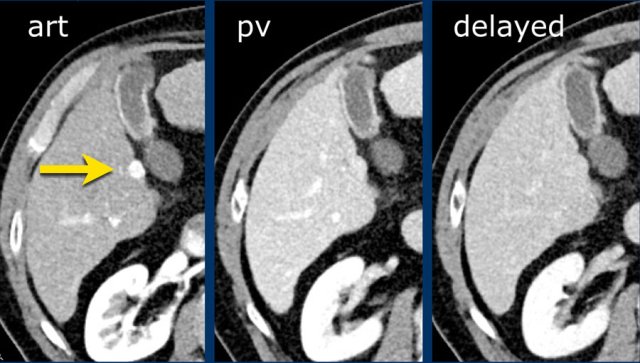

Here an image in the late arterial phase in a patient with cirrhosis.

There is an observation with non-rim hyperenhancement (yellow arrow).

In a late phase there is washout.

These are typical features of HCC.